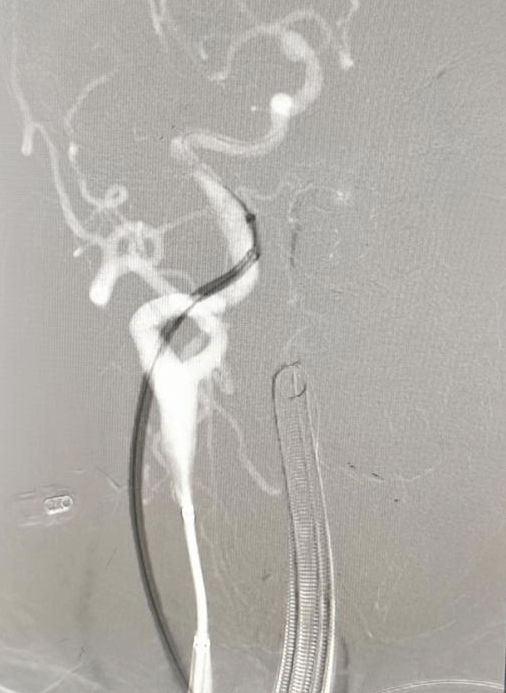

手术中造影可见右侧动脉瘤破裂小泡,为责任动脉瘤,术中予以支架辅助栓塞,考虑患者血管条件极差,若左侧同期处理,手术时间较长,容易形成血栓,增加手术风险,团队决定先处理责任动脉瘤,左侧后交通动脉瘤择期处理。

手术过程顺利,医生们凭借丰富的经验和精湛的技术,成功完成了左侧动脉瘤的处理,手术栓塞效果令人满意。由于是未破裂动脉瘤,患者恢复速度较快,术后仅3天就达到出院标准。